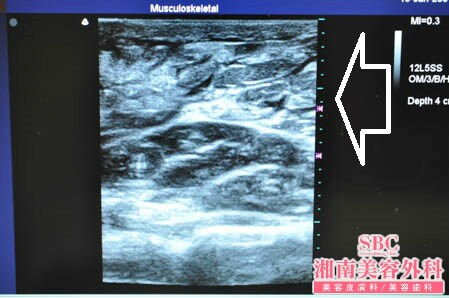

No.169954【脂肪吸引】【動画あり!】湘南美容外科・全ドクターの脂肪吸引最高責任者であるあの有名な根こそぎ竹田先生の劇的ビフォーアフター!〜遠方からご来院された患者様の二の腕を全周に渡って根こそぎ脂肪吸引する!右ちからこぶ術中3Dタッチビュー〜